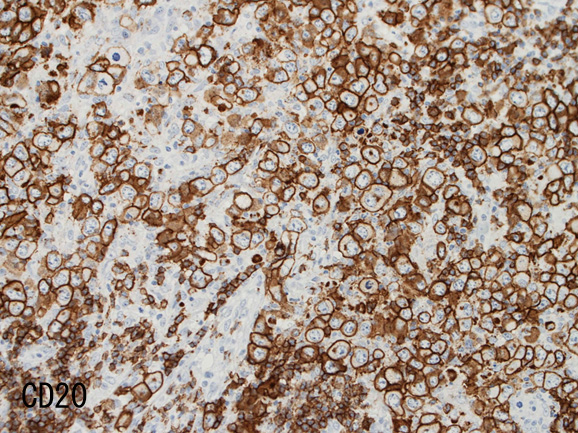

• RS細胞様巨細胞, LCLの大型細胞は B細胞マーカ(CD20, CD79a)が陽性。いずれかが消失することもある。通常腫瘍細胞の50%以上が陽性となりHodgkin病との鑑別点となる。

腫瘍細胞はCD20+, CD30+, CD15-, PAX-5+, Oct.2+, BOB.1+(Oct2, BOB1は田丸先生の染色結果), EBER-ISH+, EBNA2-

背景細胞はCD3+ Tリンパ球(CD8>CD4)とCD163, CD68陽性組織球。